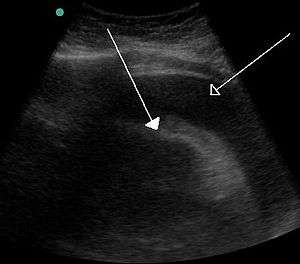

A CT scan image showing a pericardial effusion A very large hemorrhagic pericardial effusion due to malignancy as seen on ultrasound. closed arrow: the heart, open arrow: the effusion

A very large hemorrhagic pericardial effusion due to malignancy as seen on ultrasound. closed arrow: the heart, open arrow: the effusion- Pericardial effusion due to malignancy. Note bulbous heart and primary lung cancer in right upper lobe.